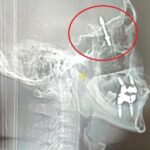

Nilüfer ilçesindeki özel bir diş kliniği, Yılmaz’a dişlerinin sallandığını söyleyerek implant önerdi. Doktor A.D.’nin uyguladığı işlem sırasında, implant vidası çene kemiğini delmek suretiyle kafatasına saplandı. Yılmaz, yaşadığı baygınlık sonrasında kliniğin aracıyla hastaneye kaldırılarak tomografi çektirildi. Çekim sonuçları, vidanın beynine kadar ilerlediğini gösterdi. Acilen ameliyata alınan Yılmaz, gerçekleştirilen zor bir operasyonla hayata döndürüldü.